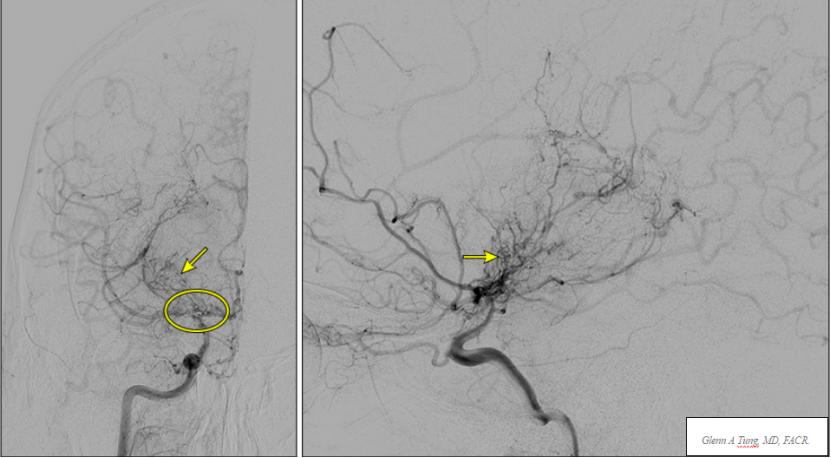

烟雾病(脑底异常血管网症)是一种不常见的脑血管疾病,其特征为颅内大动脉进行性狭窄和继发明显的小血管侧支循环形成。在血管造影时,这些侧支血管会产生特征性的烟雾状外观,最早被称为“moyamoya”,意思是蓬松的、模糊的或朦胧的,像空气中的一团烟雾,即Willis环周围单侧或双侧动脉狭窄或闭塞,伴明显的动脉侧支循环形成,导致动脉狭窄和小血管侧支循环的病理生理过程,涉及血管壁增厚和血管生成。烟雾病是一种进行性疾病,可能导致儿童和成人缺血性脑卒中或颅内出血。

通常推荐术前在颈内动脉、颈外动脉和椎动脉双侧注射造影剂进行脑血管造影,以评估血管狭窄或阻塞所在部位、侧支循环状态。